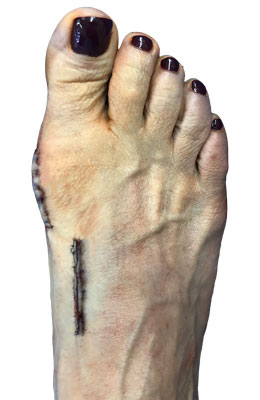

Before

Lapidus Forever Bunionectomy™ before

After

Lapidus Forever Bunionectomy™ after

Lapidus Forever Bunionectomy™

Jamie is a 53-year-old nurse who was having trouble with pain in her foot and arch and a painful bunion. Our Lapidus Forever Bunionectomy™ was utilized to correct her bunion and to stabilize her foot, arch and of course big toe joint. Jamie was back at work at 10 weeks post-surgery with full function and no pain (she didn’t even take an anti-inflammatory like ibuprofen).